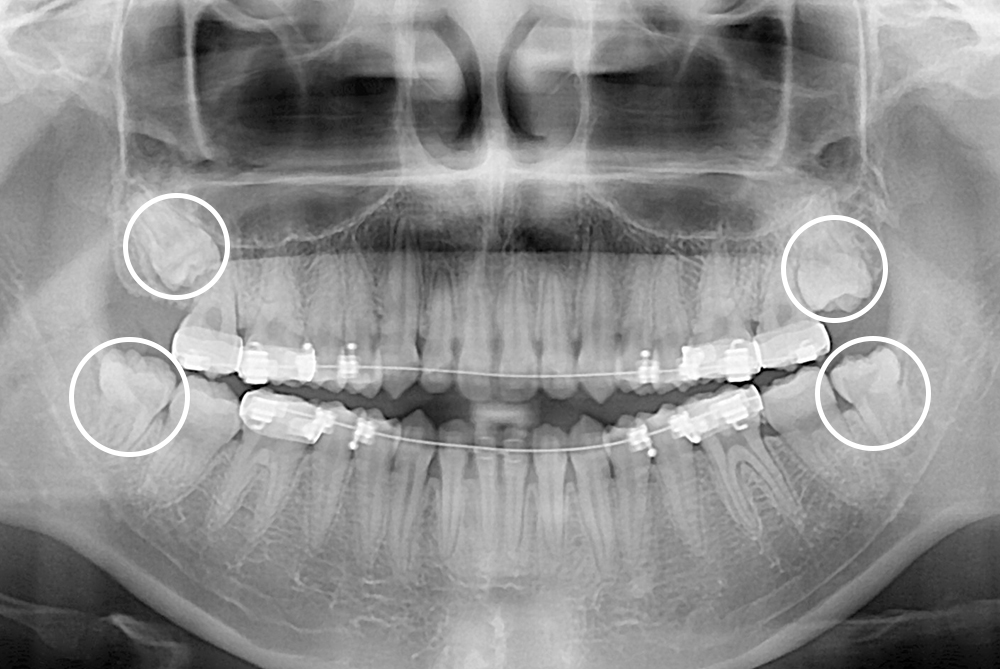

[사랑니] 매복 사랑니 발치

치료후 : 2017-07-14